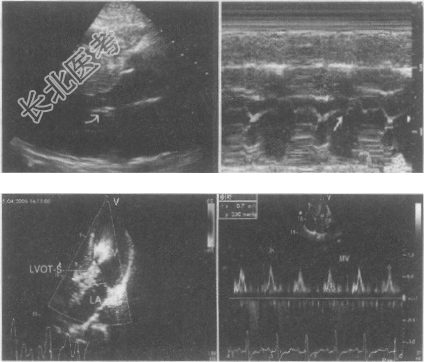

- 多项选择题1.患者行超声心动图检查,如下图,描述正确的有哪些

A、CD段呈吊床样改变

B、二尖瓣上出现异常团块样回声

C、左室扩大,呈弥漫性室壁运动异常

D、左室呈节段性室壁运动异常

E、室间隔非对称性肥厚

F、SAM征

G、E/A<1

H、彩色多普勒见左室流出道五彩血流束射向主动脉